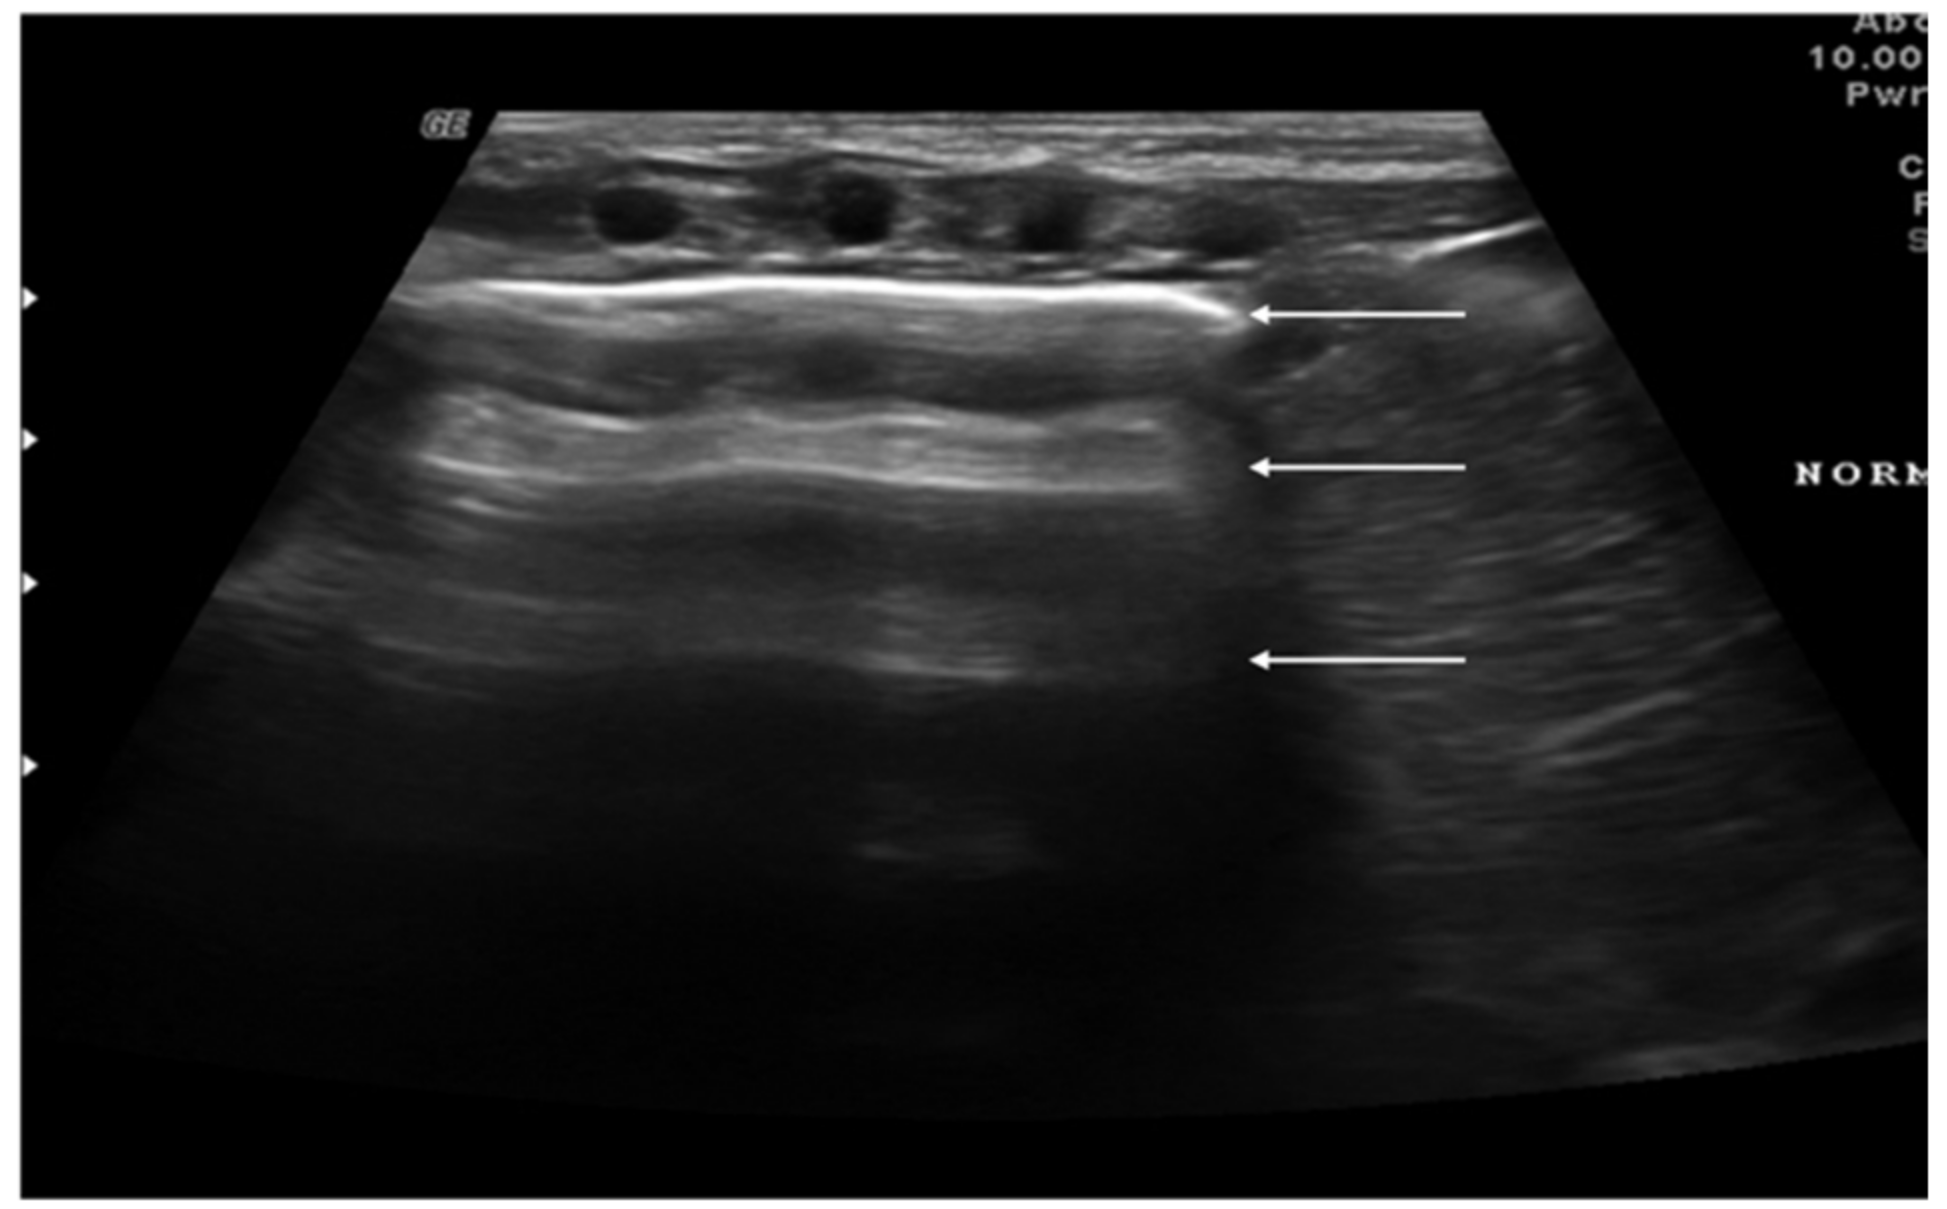

2. Technique and Equipment

3. Lung Ultrasound Findings in Healthy Subjects